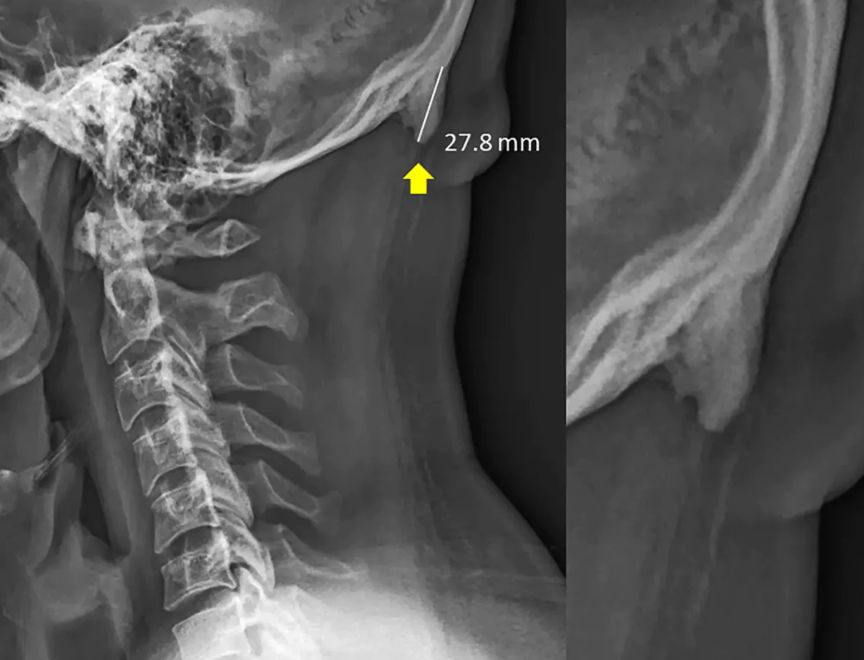

“注意啦!注意啦!看手机看多了,脑袋后面可能会长角!”

这个研究来自澳大利亚日照海岸大学的一个医生,David Shahar。他在过去20年从医的经历中,发现越来越多的人,在后脑勺窝里、颈子上面的地方,出现了一个小小的凸起。这玩意儿,学名为“枕外隆凸”(external occipital protuberance)。他发现了这个现象之后,和同事一起“看了各个年龄的1200多张X光片”,发现在18-30岁的人中,这块小骨头出现的频率“异常高”。最大的一个枕外隆突案例,“角”甚至凸出来了接近3厘米。

然后,判定长出枕骨隆突(原 paper 根本没说“长角”,毕竟动物的角和骨骼的成分根本不同)的标准在10毫米,只要超过这个值,就在数据中算作是阳性,而不一定真的长“出来”了那个东西,文中配图里的案例其实非常极端。研究者把这些X光片按年龄和性别分了组,发现年轻人当中长出枕骨隆突的人要多一点点:35%的30岁以下的年轻男性有这个隆突,而在30-50岁的观察者中,此比例不到15%。